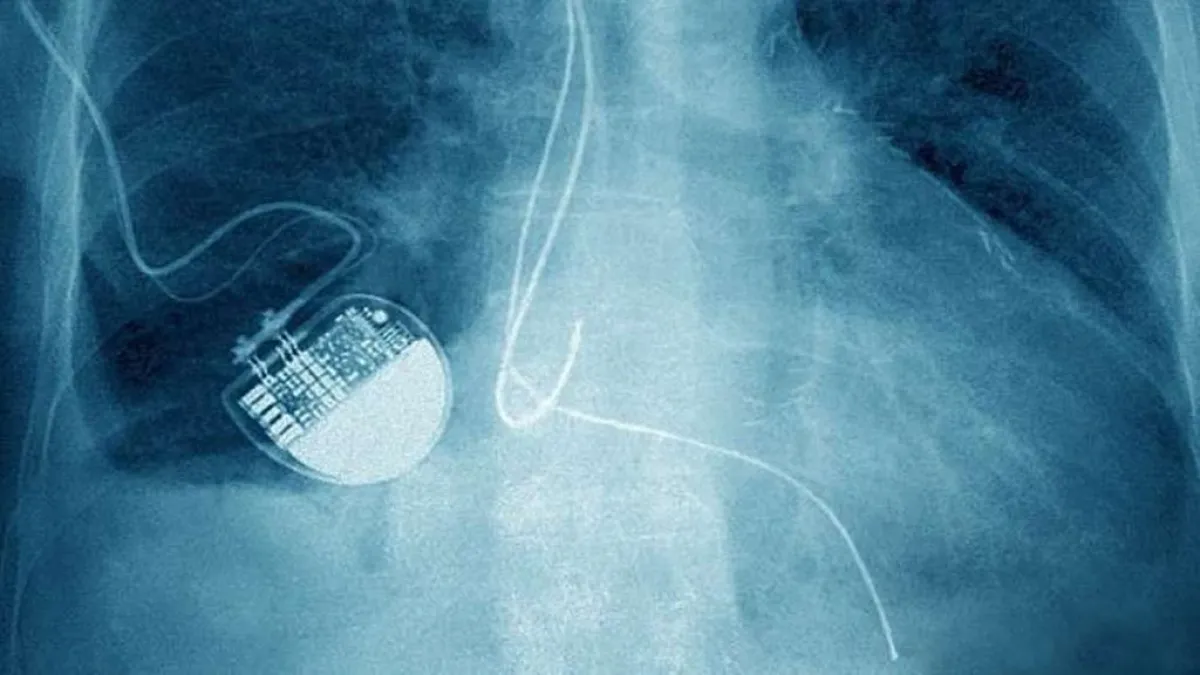

حذر تقرير جديد صادر من الأكاديمية الملكية للمهندسين من أن الهاكرز يمكنهم قتل عدد من المرضى عن طريق إيقاف أجهزة تنظيم ضربات القلب أو مضخاته.

وأكد التقرير الجديد أن عدد أجهزة الرعاية الصحية المعرضة للقرصنة في تزايد، وهي بمثابة بوابة للفيروسات التي يمكن أن تشل عمل المؤسسات الصحية الوطنية أو الإدارات الحكومية.

ومن جانبه فقد شدد البروفيسور نيك جينينغز، معد التقرير، على أنه «إذا لم يتم التعامل مع هذه المشكلة فسيكون لها عواقب وخيمة على سلامة المرضى، وهذا قد يؤدي إلى الوفاة».

وحذر جينينغز، من مخاطر الأجهزة الذكية التي يمكن التحكم بها من الهواتف المحمولة، مؤكداً، أن «هناك الكثير من الأجهزة التي يصعب على المستخدمين في الوقت الحالي تأمينها، مما يشكل خطراً يهدد حياتهم».